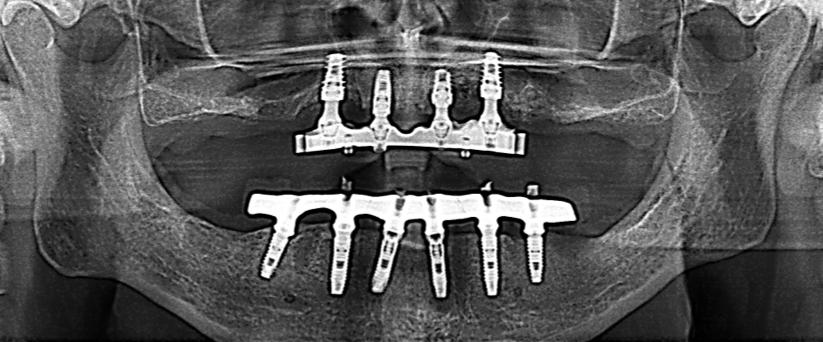

Fig 3 - Fig 4 : Paz F. aa 12

Il 13 ed il 23 sono inclusi in posizione alta, mesioangolati, con associate ampie cisti follicolari.

Il 13 è visibile dalla sezione radiale 21 alla 26.

La cuspide di 13 è craniale al 12.

Le cisti follicolari assottigliano, e a destra in parte discontinuano, i tavolati corticali vestibolare e palatale.

Si rileva inoltre rizalisi di 12. 21. 22 relative alla estensione delle lesioni cistiche.

Fig 5 - Fig 6 : Paz F aa 16 Ricostruzione panorex e sezioni radiali dell’emiarcata sinistra.

- Il 23 è in trazione ortodontica per inclusione alta in posizione mesio-trasversa, contiguo al pavimento della fossa nasale sinistra ed al pavimento del seno mascellare sinistro.

L’apice radicolare di 23 si impegna nel pavimento del seno mascellare sinistro; la cuspide erompe in versione vestibolare, craniale all’apice radicolare di 24.